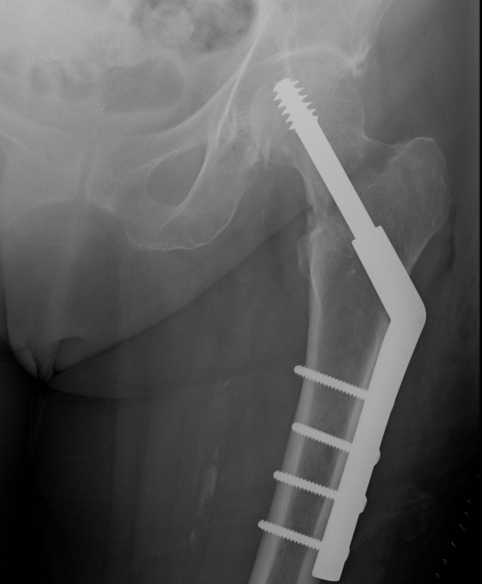

Dynamic hip screw

Mechanism

Plate is a lateral tension band whilst the sliding screw allows controlled fracture impaction

Technique

- traction table with anatomic reduction

- traction, adduction, internal rotation

Lateral approach to femur

- elevate vastus lateralis and control bleeding from perforators

Guide wire

- centred in femoral head in 2 planes

- tip-apex distance < 25 mm

Measure angle

- wire in centre of neck / centre of head

- usually 130o prosthesis

Ream to within 5 mm of end of wire

- tap

- insert screw / tip apex distance < 25 mm

- attach plate